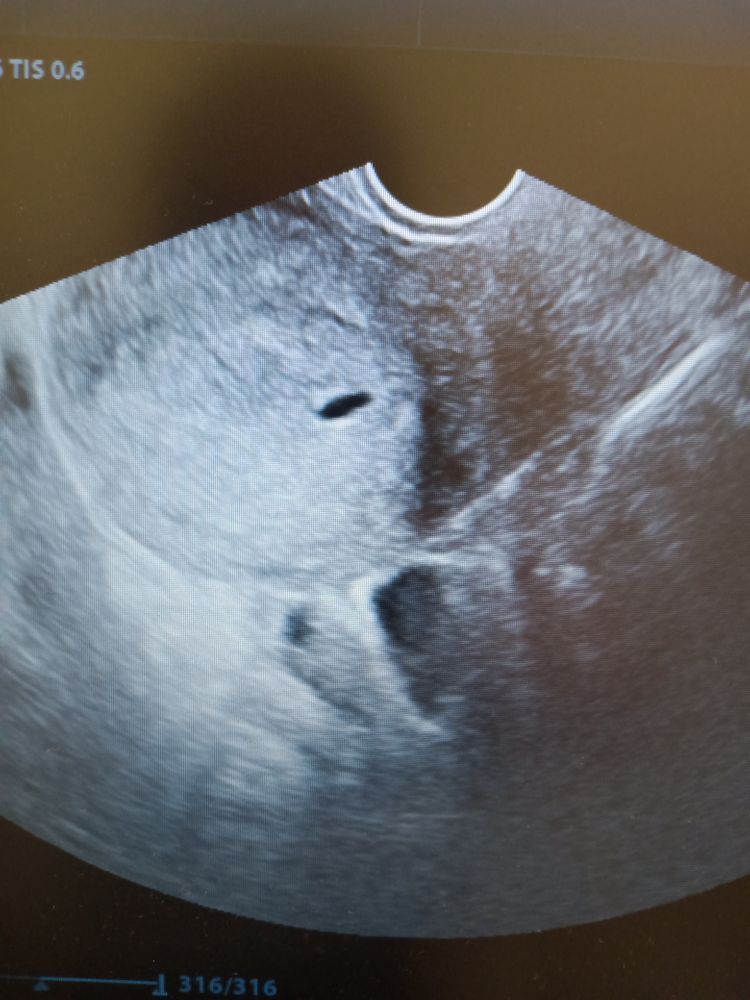

Мама мальчика (6 лет), жду мальчика, 8 неделя Пенза

Тянущая боль в правом боку

Я конечно доктор ветеринар 😁 но в узи тоже кое что понимаю …. У вас вроде как ПЯ ….. а тянет … у меня тоже на 1-2 неделе задержки тянуть начало , как будто мес должны начаться …. Проконсультировалась , сказали что это перестройка там происходит …. По этому это норма , главное чтоб выделений кровяных не было ,вот у меня они были … но это Г в Жк наковыряла на мазки, а я вообще не в курсе была, что нужно либо в начале отказываться, Ну или идти к адекватному доктору , а не к коновалу 🙈

Все хорошо у вас, тянущие боли в 1 триместре это нормально. Главное что бы никаких кровянистых розово-красных выделений не было, а так же режущих и острых болей. В вашем случае скорее всего активно работает ЖТ, не переживайте.

У меня тоже тянуло в том боку, где была О. ЖТ работает, вот и ощущения. Пусть на УЗИ у Вас все будет хорошо, прикрепление в нужном месте